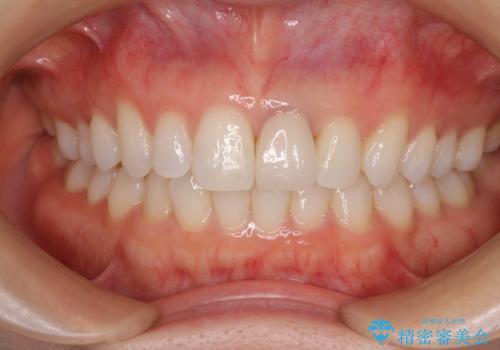

- 詰め物が欠けてしまい、虫歯かもしれないから診てほしいとのことで来院された患者様です。

精査の結果、詰め物の下に虫歯が大きく広がっているのがわかりました。

虫歯の範囲が大きく、部分的な詰め物では対応が難しいため、オールセラミッククラウンにて補綴することとしました。